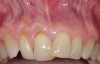

Fig 9. Two years postoperative. A complete root coverage and increase of the zone of attached and keratinized tissue is observed.

Figure 9

Fig 10. Cross-sectional view of the preoperative and postoperative (2 years). A three-dimensional increase of zone of keratinized and attached tissue is observed, restoring the lost attachment apparatus and correcting the gingival deformity in height and width.

Figure 10

Fig 11. Cross-sectional view of the preoperative and postoperative (2 years). A three-dimensional increase of zone of keratinized and attached tissue is observed, restoring the lost attachment apparatus and correcting the gingival deformity in height and width.

FIgure 11